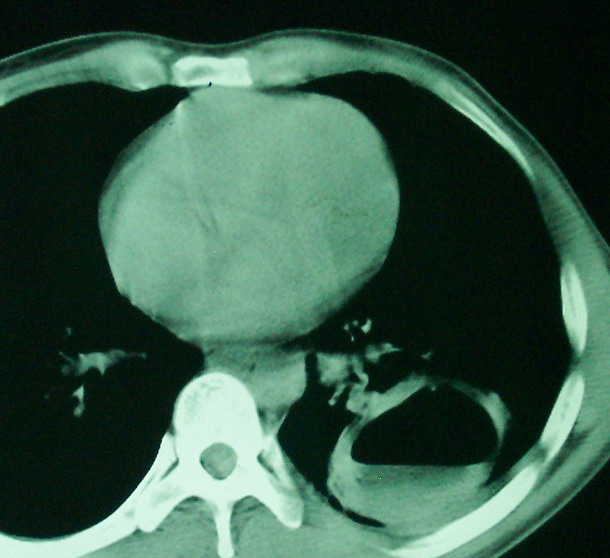

m      37y      发热   咳脓痰月余      ct肺脓肿但住院抗炎治疗后双肺内结节不知该如何解释

治疗后见左肺下野病灶较前缩小但双肺内结节影似无变化请较各位老师该如何下结论    治疗前wbc14.5 治疗后wbc 11.0

空洞内可见小结节样密度影考虑合并真菌感染

我看是不是可以两元化来解释,左肺下叶还是肺脓疡,而其余病灶考虑肺癌伴肺内转移,我看右肺上叶尖段病灶可见明显毛刺改变为原发病灶.

1、左下肺鳞癌伴两肺及纵隔淋巴结转移;

左下肺病灶除了明显的厚壁空洞 气液平外,明显见壁结节,另两肺多发小结节,综合考虑:左下肺周围性肺癌伴肺内转移.

鳞癌肺肺转移:厚壁空洞,洞壁厚薄不均,内似有壁结节,肺脓肿临床有无提示,血像如何?病灶周围很干净,没有明显渗出,很勉强?

如果你仔细的同层面对比,你会发现所有的病灶均有比较明显的吸收、缩小。病变的形态,特别是脓肿的形态、壁的厚薄、内壁均有很大的变化,均在往好的方面发展。与临床症状、血像均符合,治疗效果比较显著,就是肺脓肿并双肺的化脓性炎症灶。